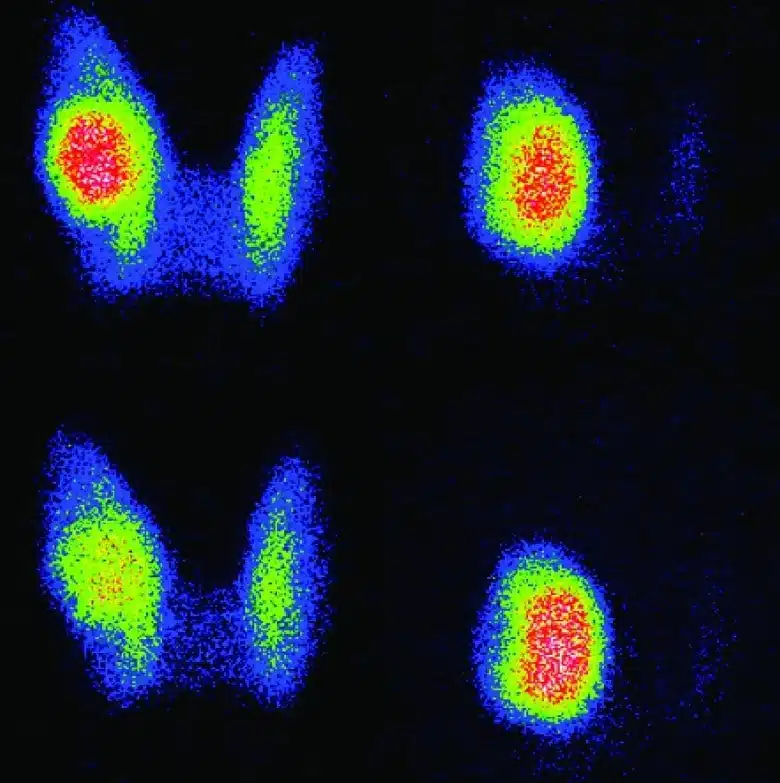

Η ονομασία τους προέρχεται από το έντονο ερυθρό (θερμό) χρώμα που εμφανίζουν στο σπινθηρογράφημα θυρεοειδούς, εξαιτίας του έντονου μεταβολισμού τους, σε σύγκριση με τον υπόλοιπο θυρεοειδή αδένα.